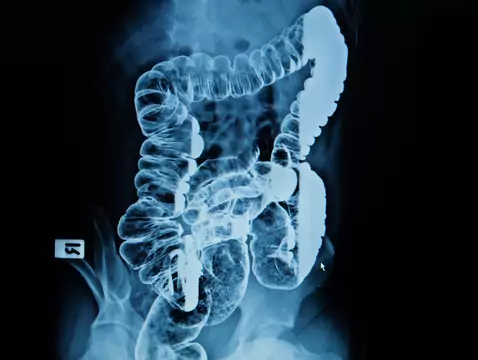

Le cancer colorectal est un néoplasme qui se développe dans le côlon, le sigmoïde et le rectum. Dans 90 à 95 % des cas, l'incidence du cancer colorectal est sporadique, les 5 à 10 % restants étant...